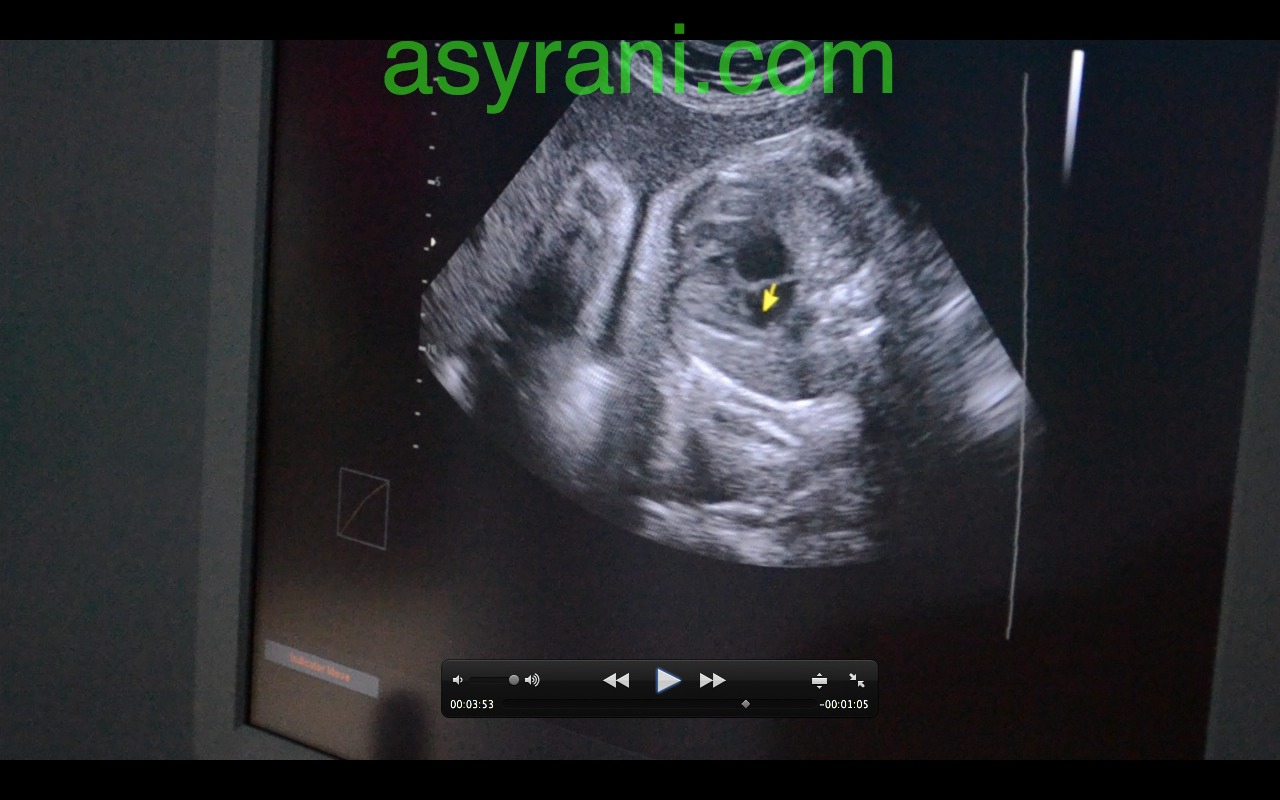

Anak panah menunjukkan Four Chamber jantung baby

Gambar Four Chamber jantung yang lebih jelas